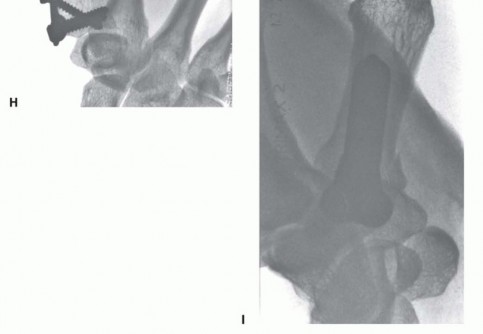

Fixation Strategies for Rolando and Comminuted Patterns

Rolando fractures present a significantly higher degree of complexity. The classical Y or T pattern often precludes simple lag screw fixation. In these instances, mini-fragment plating is the gold standard. T-plates or specialized condylar plates are contoured to fit the complex geometry of the metacarpal base. The articular fragments are first reduced and provisionally pinned, essentially converting the complex intra-articular fracture into a simpler two-part extra-articular fracture. The plate is then applied to buttress the articular fragments and bridge the metaphyseal comminution to the diaphysis.

In cases of severe, non-reconstructable articular comminution where internal fixation is impossible, joint-spanning external fixation combined with limited internal fixation (K-wires) is utilized. The external fixator relies on the principle of ligamentotaxis to restore length and align the articular fragments. Pins are placed in the trapezium (or radius) and the thumb metacarpal shaft, distracting the joint to allow for secondary bone healing while preventing collapse.